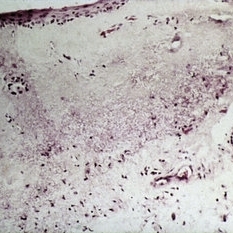

Slide 7-35

Feb 25 2019 by Lancaster Course in Ophthalmology

In interstitial keratitis, the only pathology noted is the presence of blood vessels in the deep stroma.

Condition/keywords: interstitial keratitis, stroma